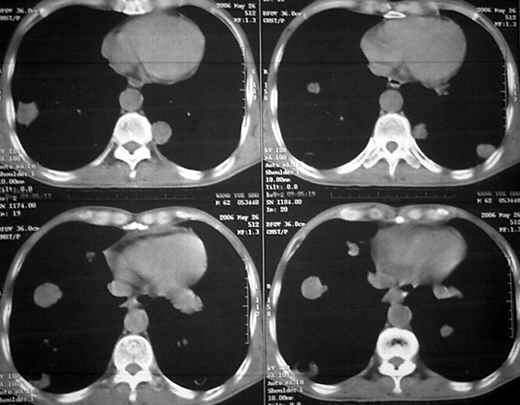

男62肺癌治疗后复查

具体治疗措施不清楚,治疗前空洞很少,请讨论空洞的性质

双肺内及胸壁旁见有多发软组织实性阴影和空洞,实性病变多见有脐凹切迹,贴近胸膜的见有胸膜凹陷征;空洞的壁多为厚薄不均,形态不规则,纵隔内见有较多肿大淋巴结,诊断为双肺内转移性病变。

肺癌肺转移,其中有空洞转移,这与放疗或化疗有关,

中华放射学杂有关于肺空洞性转移的报道。

cpm的成因尚不完全明确,可能与鳞癌中心角化物排空、腺癌黏液样退变后黏液排空、肿瘤血供不足引起坏死、肿瘤继发脓肿、化疗等机制有关【2,4,5 j,但无一种机制能解释全部现象。例如血供不足就不能解释为何空洞可见于小结节。本组小环形空洞占全部空洞的近1/4,而且不少病例中大结节未见空洞,而比其小许多的小结节却有空洞。至于化疗,虽然本组不少病例在化疗后出现空洞,但不少病例(如鼻咽癌)在首次发现cpm灶时并无化疗史,这说明化疗不能解释全部空洞的成因。更难以解释的是,为何同一病例的不同空洞却同时呈现两种截然不同的变化。因此,很可能有多种机制参与空洞形成。

由于各叶cpm灶发生率之间并无显著性差异,故可认为cpm发生与其所在部位无关。对空洞形成有何临床意义尚无统一认识,有人认为是瘤灶消散时的表现,亦有人认为空洞代表病情恶化[6,7】。本组空洞缩小或增大、消失或出现并不与病情好转或恶化保持一致,说明有无空洞或空洞大小并不反映病情变化,其临床意义不大,而瘤灶的数目及大小,特别是瘤灶实性成分的多少才可能更准确反映病情变化。